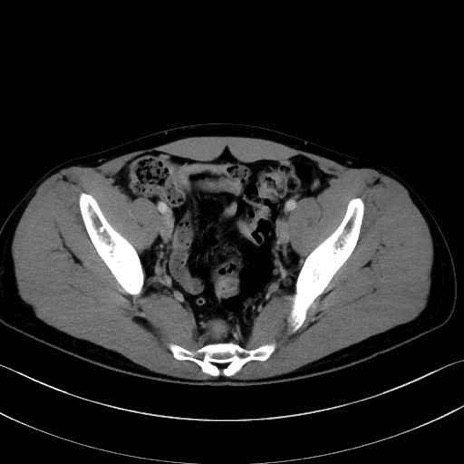

大腿筋膜張筋 (Tensor fasciae latae)